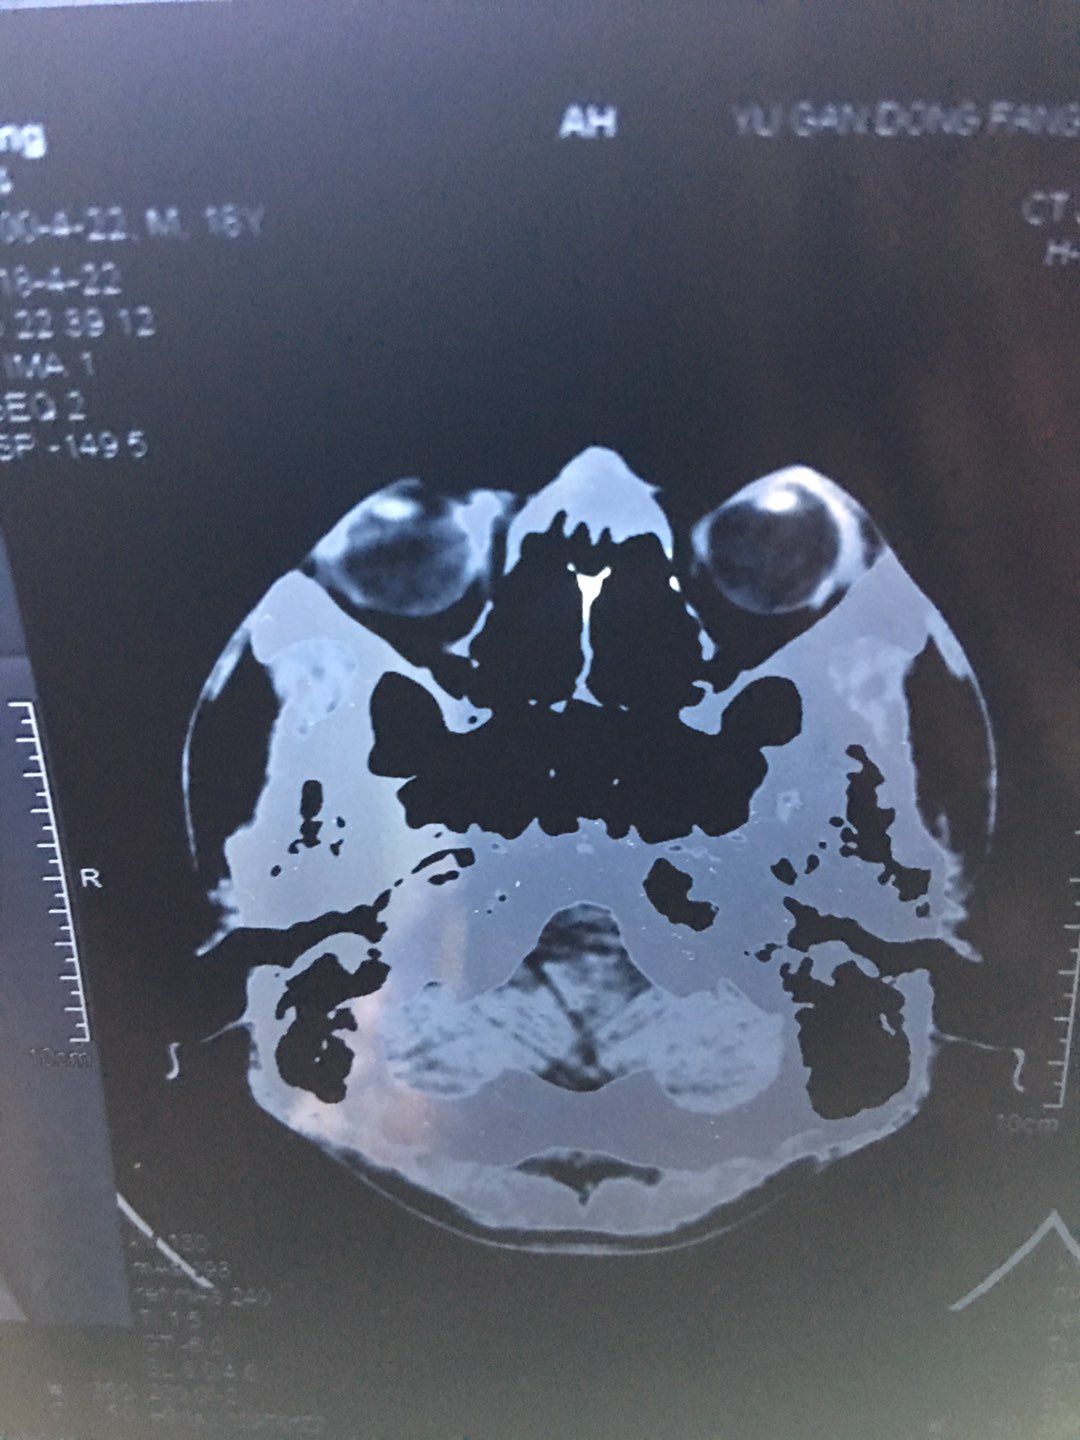

鼻中隔偏曲了吗